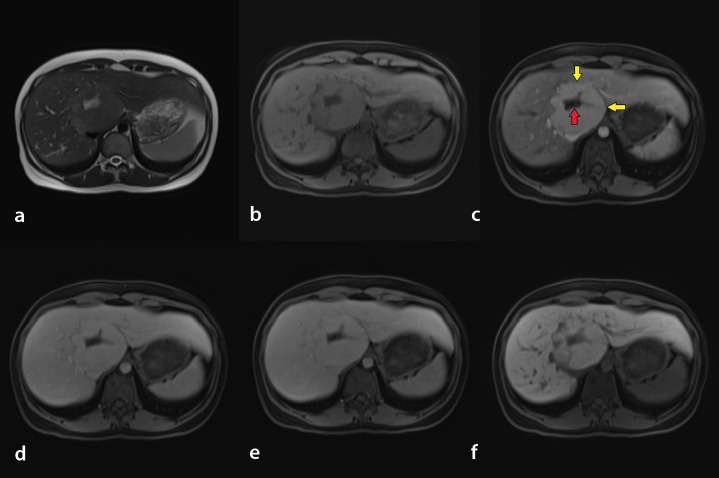

目的:本研究旨在评价人工智能(AI)在磁共振成像(MRI)诊断肝脏局灶性结节性增生(FNH)中的有效性,并与放射科医生进行比较。方法:在第一阶段的研究中,使用分割程序对60例患者(30例FNH患者和30例无病变或非FNH病变患者)的mri进行处理,并引入AI模型。在学习过程之后,将人工智能模型没有经验的42名不同患者的核磁共振成像引入系统。此外,一名放射科住院医师和一名放射科专家评估了具有相同MR序列的患者。敏感性和特异性值均来自所有三篇综述。结果:AI模型的敏感性为0.769,特异性为0.966,阳性预测值为0.909,阴性预测值为0.903。敏感性和特异性值高于放射科住院医师,低于放射科专科医师。专家与人工智能模型的结果显示出良好的一致性水平,kappa (κ)值为0.777。结论:人工智能设备诊断FNH的敏感性、特异性、PPV、NPV均高于放射科住院医师,低于放射科专科医师。随着对肝脏不同特定病变的进一步研究,人工智能模型有望在未来能够高精度地诊断每种肝脏病变。临床意义:研究人工智能为放射图像提供辅助或自动解释,并提供准确和可重复的成像诊断。

Purpose: This study aimed to evaluate the effectiveness of artificial intelligence (AI) in diagnosing focal nodular hyperplasia (FNH) of the liver using magnetic resonance imaging (MRI) and compare its performance with that of radiologists.

Methods: In the first phase of the study, the MRIs of 60 patients (30 patients with FNH and 30 patients with no lesions or lesions other than FNH) were processed using a segmentation program and introduced to an AI model. After the learning process, the MRIs of 42 different patients that the AI model had no experience with were introduced to the system. In addition, a radiology resident and a radiology specialist evaluated patients with the same MR sequences. The sensitivity and specificity values were obtained from all three reviews.